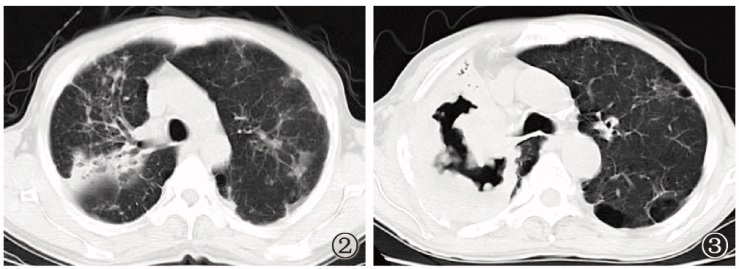

图4~9

图4~9肺结核与肺癌共病的影像学表现。 图4~6为同一患者,既往肺结核病史;图4可见患者右肺上叶后端残留支气管扩张;图5显示患者7个月后支气管扩张区呈黏液嵌塞征表现,周围散在结节影;图6显示患者13个月后支气管扩张的管腔内软组织病变生长呈典型支气管铸型征表现;行支气管镜组织活检,病理诊断为鳞癌;同时,气道分泌物抗酸杆菌涂片阳性,提示结核病复发。图7~9为同一患者,诊断为左上叶活动性肺结核,涂阳,初治。图7为患者治疗前,右肺中间段支气管未见明显异常;图8为患者经抗结核治疗后病变逐渐吸收,但右肺中间段支气管略见狭窄,未采取措施;图9为患者抗结核治疗5个月后复查CT,可见肺结核病变显著吸收,中间段支气管管壁狭窄直至闭塞,不符合结核病转归病程,呈“矛盾现象”;支气管镜活检病理诊断为鳞癌。